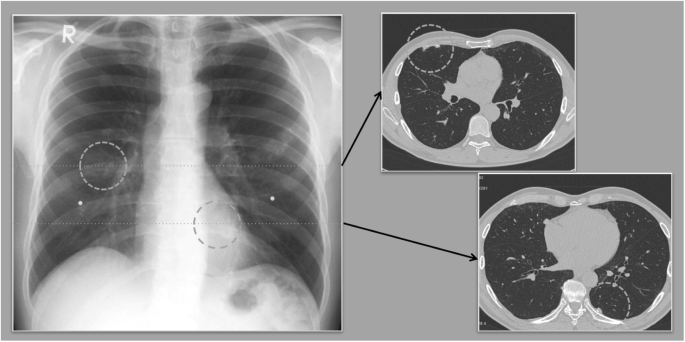

Some work-related respiratory diseases have characteristic radiologic features suggesting the diagnosis. However, definite diagnosis requires combination of occupational history, medical examination and imaging features, interpretation of radiologists is needed for accurate diagnosis. In OSH there is a need for radiologists who are specialized in occupational diseases diagnosis. The chest X-ray (CXR) only serves the role of an epidemiological instrument, since it only helps finding the disease. The CXR does not find the correlation between lung function and compensation.

Changes in the lung caused by the retention of and the reaction to inhaled dust (organic as well as inorganic) are classified into two, those with Granuloma (e.g. Silicosis) and without Granuloma (e.g. asbestosis). The lack of visible vessels distribution seen in a normal x-ray can be a potential sign of fibrosis. Distribution of pulmonary diseases can suggest the likely diagnosis, conditions with upper zones preference include, Silicosis, TB, Respiratory bronchiolitis interstitial lung disease (RB-ILD), Smoking related emphysema, Langerhans cell histiocytosis, mucoviscidosis. Sarcoidosis is known to show middle zones preference, while lower zones preference is observed with usual interstitial pneumonia (UIP)-Pattern idiopathic pulmonary fibrosis (IPF), asbestosis, collagenosis, nonspecific interstitial pneumonia (NSIP), bronchiolitis obliterans; no predominance is expected with hypersensitivity pneumonitis or extrinsic allergic alveolitis (HP/EAA) and lymphangiosis.

Chest radiography is an important tool for clinical evaluation of pulmonary diseases, especially infectious lung diseases, diffuse lung diseases or the interstitial lung diseases and neoplastic diseases. Chest radiographs are useful in clinical care, assisting in both diagnosis and evaluating response to therapy. However, pattern recognition on CXR requires important clinical skill for evaluation of acute and chronic lung diseases. Chest Computed Tomography (CT), especially as High-resolution CT (HRCT), provides significantly improved information and is essential for a definitive diagnosis. Nevertheless, the plain chest films cannot be replaced, also for reasons of availability and the resulting costs.

The finding of pleura can confuse with presence of a tumor, requiring CT scan to differentiate between the two (Fig. 1). In order to be able to compare the localization of a finding in the chest film with the computed tomographic image, the 3 zones of the ILO-classification (upper, middle and lower zones) have to be transferred virtually to the regions in the CT.

In conclusion, imaging in the diagnosis of work-related respiratory diseases plays a role as tool for epidemiology and monitoring. Chest X-ray as a basic study is available everywhere and affordable. Low Dose-Vol-CT is essential for the plausibility of diagnosis. Quality management program is essential for workplace assessment, personal medical and professional history, monitoring of the quality of radiological examination and diagnosis. Radiographic Imaging has limitations, especially without HRCT, as it is not diagnostic gold standard; airway disorders are not always seen, functional impairment not well evaluated or assessed and cannot provide certainty about the etiology of observed findings due to limited lung response patterns.